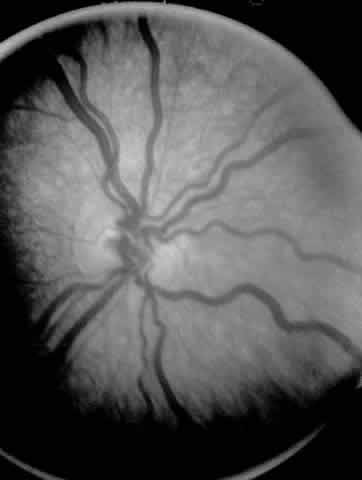

ROP accounts for a large number of retinal detachments in the pediatric population. The International Classification of Retinopathy of Prematurity helped greatly to improve communication about, and consequently treatment of, ROP. It describes affected eyes in terms of stage, zone, and absence or presence of plus disease18 (Figs. 1, 2, and 3). Screening of premature infants is an important feature in the care of ROP, which is perhaps the most significant and enduring finding of the Cryotherapy for Retinopathy of Prematurity Study (Cryo-ROP Study).19

Fig. 3. Dilated and tortuous vessels in the posterior pole, which by definition is plus disease.